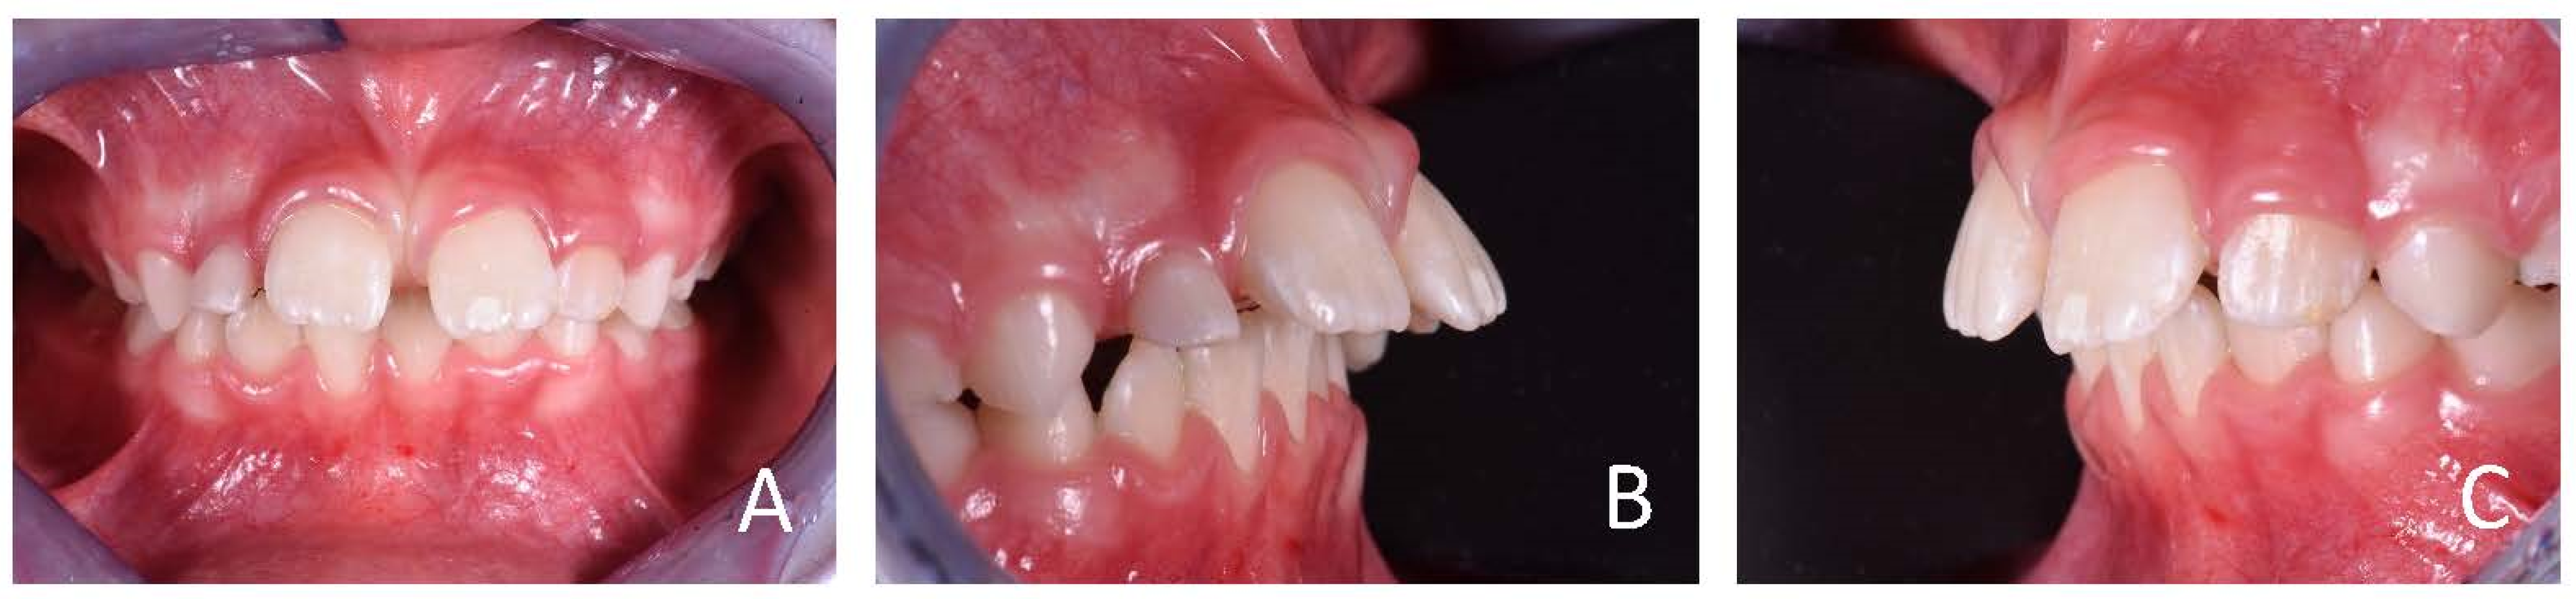

3.1. Clinical Case #1

3.2. Clinical Case #2

3.3. Clinical Case #3

3.4. Clinical Case #4